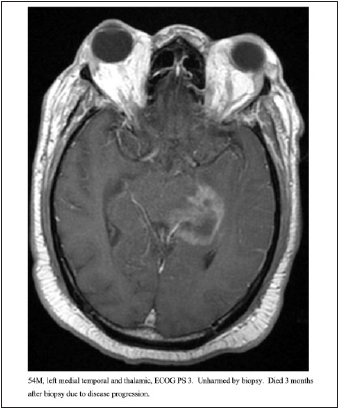

This retrospective analysis characterized the iatrogenic hemorrhage rates for stereotactic biopsy and overall survival in a large series of patients at one institution. All of these patients had unresectable high-grade gliomas, and all were managed by experienced tumor surgeons. The term “unresectable” is debatable and beyond the scope of this paper. Figures 2-4 show imaging for several patients included in this cohort. Data on outcomes for unresectable high-grade gliomas following stereotactic biopsy is very limited. We identified variables associated with increased risk of poor postoperative outcomes. Age was a strong predictor of 60-day mortality and overall survival. PS discriminated for 60-day mortality and overall survival following biopsy, but this did not reach statistical significance. Neither PS nor age had any prognostic value for risk of bleeding given our few bleeding events. Performance status is a well-established prognostic factor in patients with glioma. One previous study showed that glioblastoma patients with preoperative Karnofsky Performance Scale (KPS) ≤ 50 had a median OS of 1.8 months, while patients with KPS 60, 70, 80, and ≥ 90 had a median OS of 2.8, 4.8, 7.3, and 17.2 months, respectively (HR=1.24, 95% CI=1.06–1.44, P=0.006). The total cohort in this study was 206 patients, 93 of which who underwent surgical resection and 113 who underwent biopsy. Our series did not demonstrate PS significantly affecting prognosis, likely due to the fact that all patients in our series had unresectable lesions, and OS was very poor for the entire population. Age had the strongest effect on the risk of death within 60 days and overall survival following biopsy. Older age predicted significantly higher likelihood of death within 60 days and worse OS. This is consistent with existing literature showing that increasing age is a negative prognostic factor for glioblastoma, although there is very limited data looking at outcomes only for unresectable high-grade gliomas. Our data shows that combining PS and age provides superior prognostic information rather than age or performance status alone. We identified one subgroup that significantly outlived the other three subgroups. PS 0-2 and ≤ 65 had a much-improved median OS compared to the other groups, while PS 0-2 and age > 65, PS 3-4 and age ≤ 65, and PS 3-4 and age > 65 all had similarly very poor outcomes. The majority of studies describing the risks of stereotactic biopsy consider the morbidity and mortality directly attributable to the procedure itself. By tracking mortality within 60 days and OS, this study encapsulates patients who were harmed by the procedure and those who experienced clinical deterioration or death due to natural progression of their disease. These patients with an extremely poor prognosis likely represent a patient population for which stereotactic biopsy is at best, futile, and at worst, harmful. Our data suggests that if a patient is over 65 years old or has an ECOG PS of 3-4, their median OS is only 3 to 4 months, and these patients are likely better served with hospice care and/ or empiric radiation rather than a biopsy.

Figure 3:54M, left medial temporal and thalamic, ECOG PS 3. Unharmed by biopsy. Died 3 months after biopsy due to disease progression.